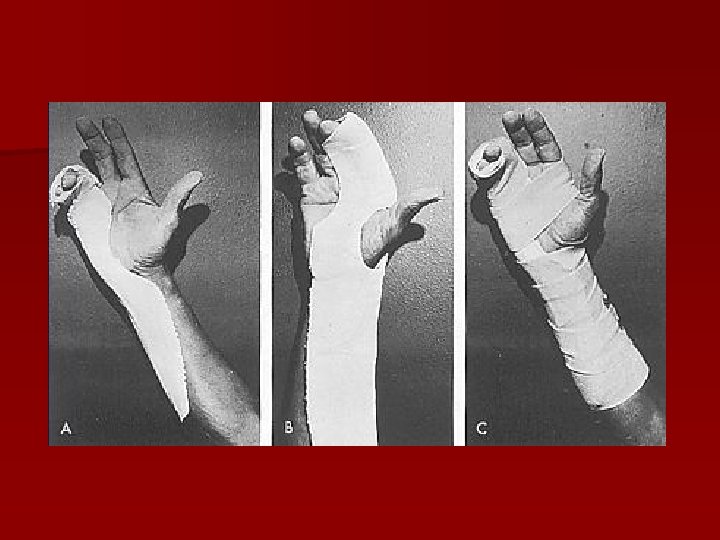

Imobilizare – metoda Burkhalter, Reyes